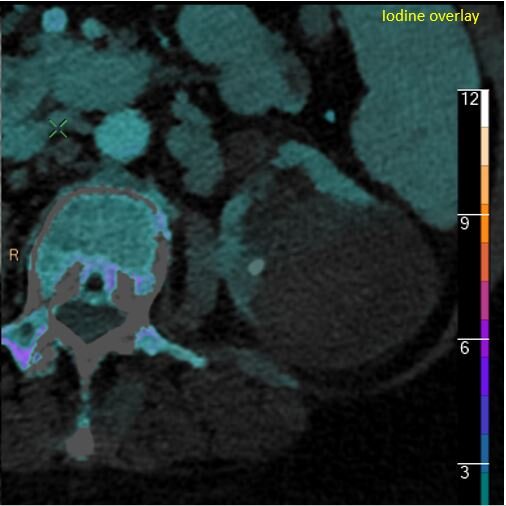

Iodine overlay: Absent iodine uptake proves this is not neoplastic.